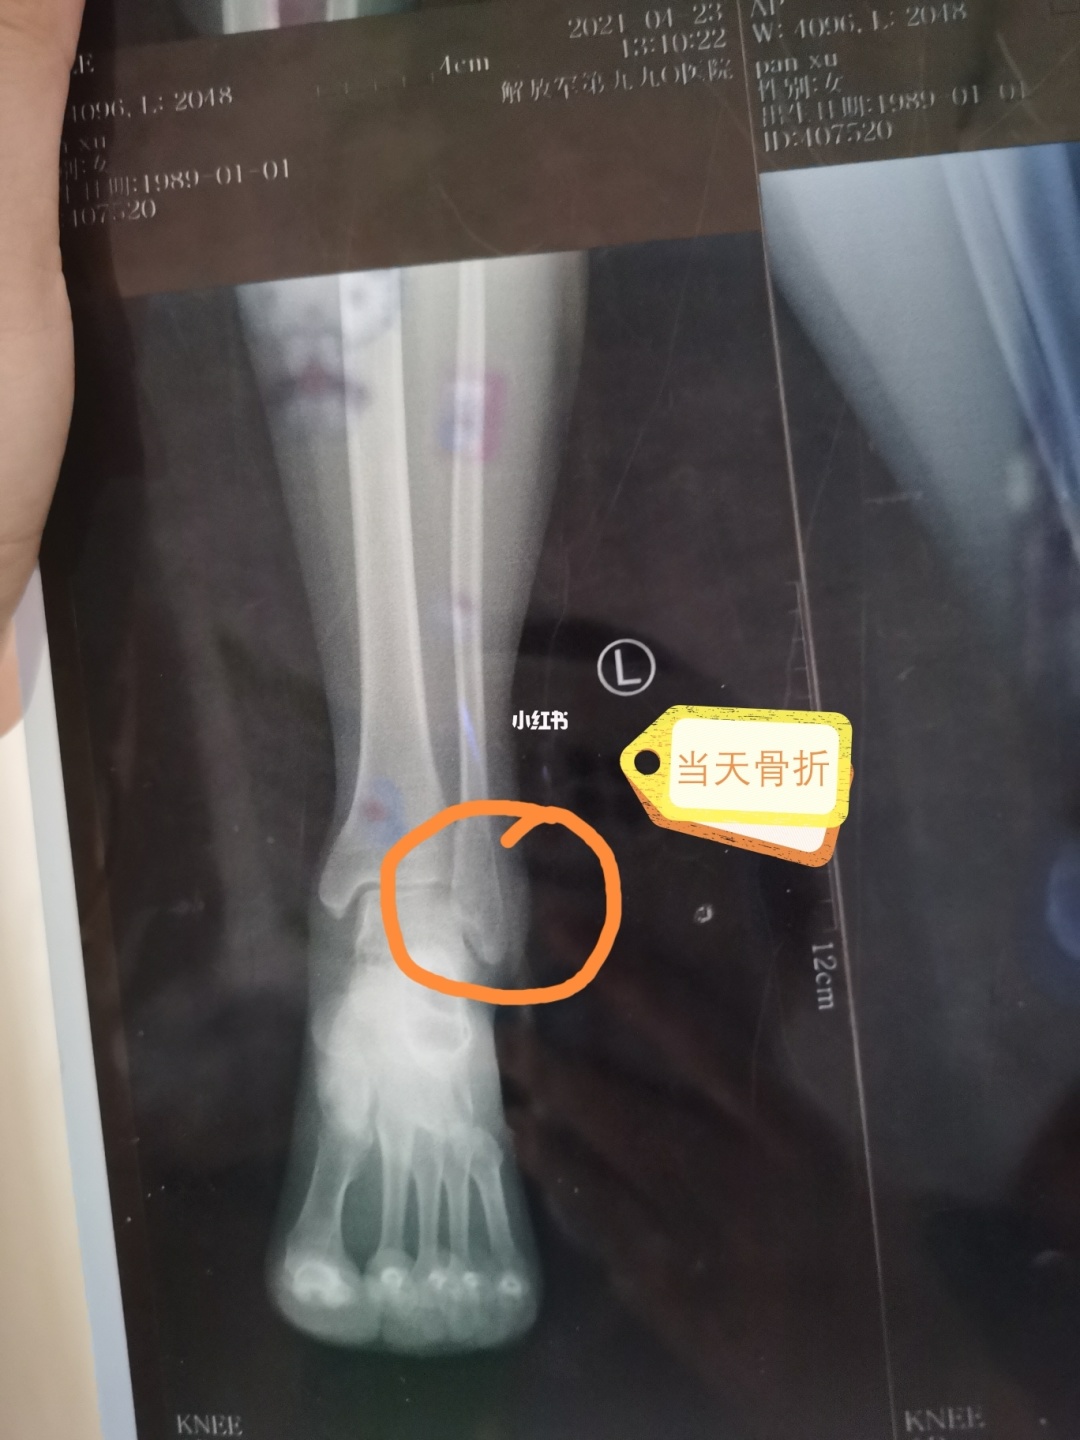

一旦钙严重缺乏,骨头就变得疏松起来,坚硬度下降,就形成了老人中常见的骨质疏松症。对老年女性尤其如此,因为雌激素对于成骨过程至关重要,绝经期女性雌激素分泌大幅度下降,导致骨质变得像蜂窝一样,疏松易断。在全世界范围内,患骨质疏松症的人群中,80%是女性,其中50岁以上的大约占1/10,70岁以上的占1/5,而男性的这个比例大约是7%。